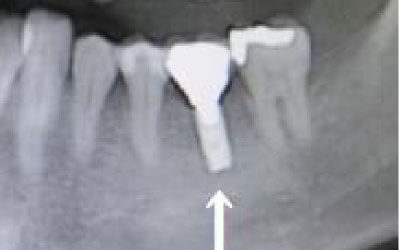

CTを使うと、骨や歯の状態を立体的に確認でき、正確な距離も測定できます。

骨の厚さや傾き、神経の位置などを事前に詳しく把握することで、安全にインプラント治療を行うことができるのです。

しかし、当院では事前にCT撮影を行い、神経までの距離を三次元的に正確に把握した上で治療計画を立てるため、リスクをしっかり回避できます。

さらに、骨を削りすぎないようにするための専用のストッパーも導入しており、安全性には十分に配慮しています。